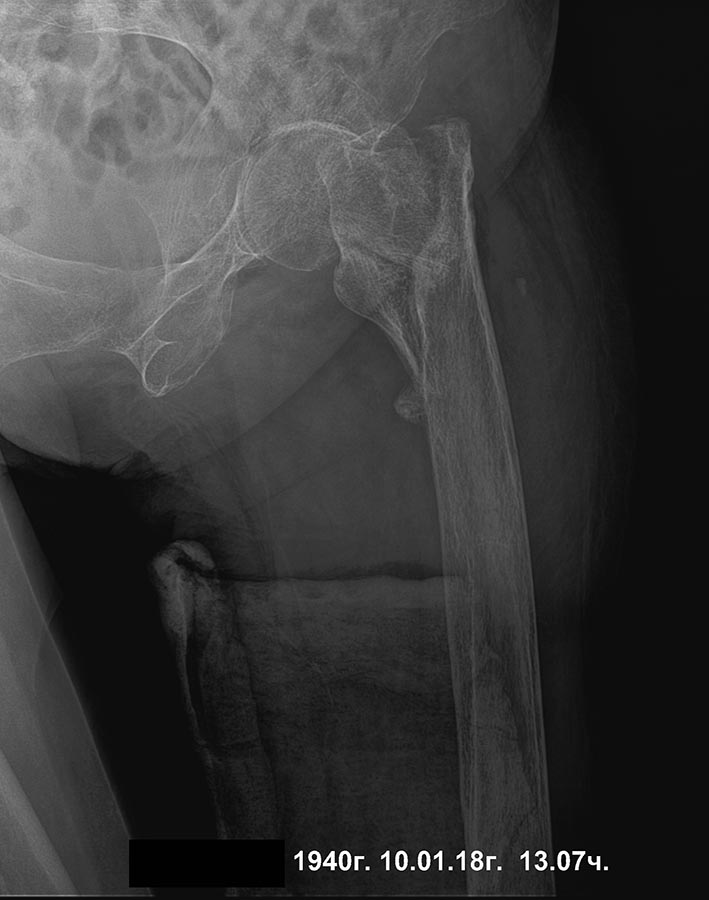

[Ortho] сросшийся чрезвертельный и перелом н\3 бедра

уважаемые коллеги, прошу высказаться по такому случаю, 4 мес назад

чрезвертельный перелом, 2 нед назад при попытке ходьбы с ходункамии нога

подкосилась (укороч порядка 4-5 см) и сломала нижнюю треть. Какие

мнения, как сделать поаккуратнее, бабушка 78 лет.

Состояние здоровья среднее.